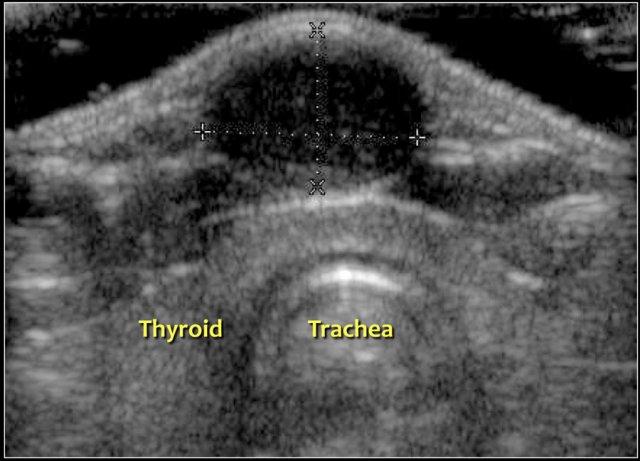

Siêu âm thường đủ để chẩn đoán.

Luôn tìm kiếm sự hiện diện của tuyến giáp bình thường và chụp ảnh tuyến giáp.

Nang ống giáp lưỡi có thể không có âm vang hoặc giảm âm vang với các tiếng vang bên trong, do nhiễm trùng, xuất huyết hoặc thành phần chứa protein.

Phần lớn nang ống giáp lưỡi nằm trong vòng 2 cm so với đường giữa.

Đây là hình ảnh cắt ngang của một nang ống giáp lưỡi giảm âm có một số tiếng vang bên trong nằm ở đường giữa.

Đây là hình ảnh cắt ngang của một nang ống giáp lưỡi trống âm nằm ngay bên trái đường giữa.